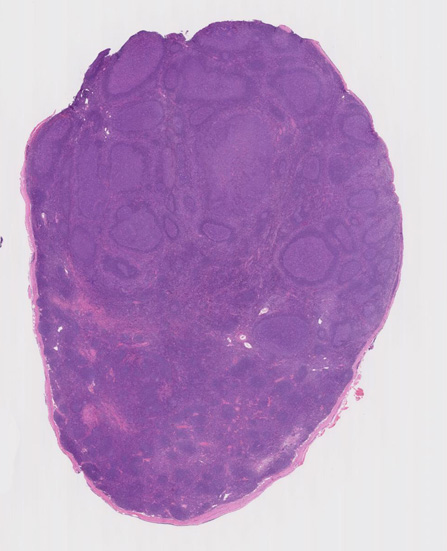

大きな胚中心を持つ多数のリンパ濾胞が見られる。胚中心の辺縁は不明瞭でマントル層も薄くなっている。1カ所マントル層リンパ球の侵入によりバラバラになった巨大な胚中心が認められ, macrofollicular patternと記載されるPTGCです。

鑑別にあがるfollicular lymphoma floral variantは全ての濾胞が腫瘍性であり, 本症例では除外可能と考える。

Diagnosis: Reactive lymphadenitis with PTGC